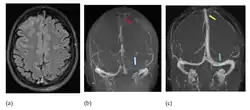

Wegen dieser Schwierigkeiten wird bei entsprechendem Verdacht frühzeitig eine Schnittbilddiagnostik des Schädels empfohlen. In der Computertomographie oder Kernspintomographie sind Infarktzonen und Blutungen erkennbar, die nicht den bekannten arteriellen Versorgungsgebieten entsprechen. In der nativen Computertomographie (ohne Kontrastmittel) kann sich das Gerinnsel im Sinus hell, also dichter als das umliegende Gewebe (hyperdens), darstellen. Mit Kontrastmittel lassen sich sowohl in der Computertomographie wie auch in der Kernspintomographie die Gerinnsel direkt als Aussparung in den ansonsten kontrastierten Sinus meist gut erkennen. Die Diagnose kann gelegentlich schon im CT gestellt werden. In der Regel ist aber eine CT-Angiographie oder Kernspintomographie erforderlich. Mittel der Wahl zur Diagnostik von Venen- und Sinusthrombosen ist die Kernspintomographie, sie ist aber nicht immer verfügbar. Die Kernspintomographie sollte auch suszeptibilitätsgewichtete Bilder und eine Time-of-flight-Angiographie enthalten, um alle Thrombosen zu erfassen.[23] Die interventionelle Angiografie mit einem Katheter kommt nur noch in Ausnahmefällen in Betracht und spielt im deutschsprachigen Raum fast keine Rolle mehr.[2] Bei Neugeborenen wird die Ultraschalluntersuchung des Gehirns über die Fontanelle vorgezogen.[5]

- Bildgebung bei zerebralen Thrombosen (zum Vergrößern Bilder anklicken)

-

-

Axiales SWI-Bild der scheitelnahen Duravenen. Die Thrombose ist im rechten Bild blau hervorgehoben.

Axiales SWI-Bild der scheitelnahen Duravenen. Die Thrombose ist im rechten Bild blau hervorgehoben. -

-

Andere SVT (gelbes Kreuz), Einzelschicht aus einer MR-Angiographie.

Andere SVT (gelbes Kreuz), Einzelschicht aus einer MR-Angiographie. -

-

CT ohne Kontrastmittel (links), und der gleiche Fall im MR mit Kontrastmittel. Thrombus durch roten Pfeil gekennzeichnet.

CT ohne Kontrastmittel (links), und der gleiche Fall im MR mit Kontrastmittel. Thrombus durch roten Pfeil gekennzeichnet.